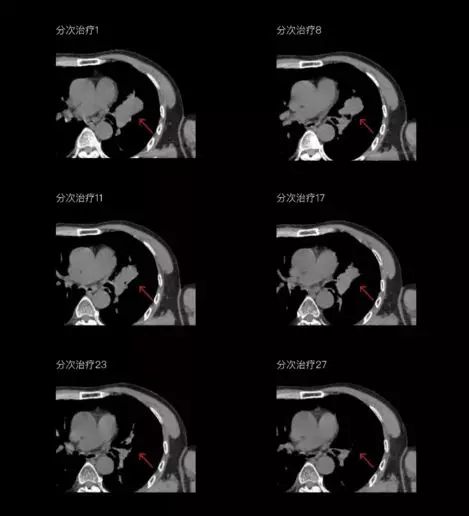

聯(lián)影CT-linac全程監(jiān)測(cè)治療過(guò)程病灶的變化,及時(shí)調(diào)整和優(yōu)化治療方案